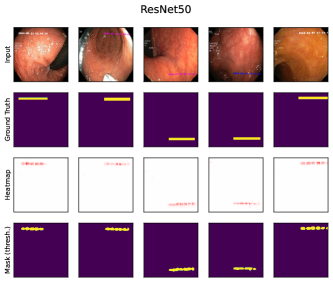

where denotes element-wise multiplication. This yields a heatmap that can be used as a soft mask or converted to a binary segmentation mask, for instance using thresholding techniques like Otsu’s method [57]. An example is shown in Fig. 2 (right), showing soft masks as heatmaps from concept-conditioned local attribution scores, along with binary masks for three known data artifacts: rulers and band-aids for skin cancer detection, and pacemakers in chest radiographs.

6.4 Spatial Bias Localization

To spatially localize biases in input space with CAVs, we compute local explanations for the element-wise product of latent activations and concept direction (see Eq. 2). We use the controlled artifacts, specifically timestamp (HyperKvasir) and micropscope (ISIC2019) with ground truth concept localization masks for evaluation. We compute (1) the percentage of relevance within the ground truth mask and (2) the Jaccard index, or Intersection over Union (IoU), of the binarized localization mask with the ground truth. In Fig. 9, we report both metrics using CAVs computed on different layers of VGG16 and ResNet50. The layer choice for concept representations is key, as for example middle layers perform better to localize timestamps and earlier layers are more effective to localize the microscope. In comparison with Fig.7, we find that the optimal layer for bias localization may differ from the one for sample retrieval. Interestingly, the IoU for the microscope artifact is consistently low, as models primarily focus on the border of the circle instead of the entire area, as indicated by qualitative results in Appendix A.6.3. Unlike artifact relevance, the IoU metric also measures how much of the expected areas the computed mask does not cover.